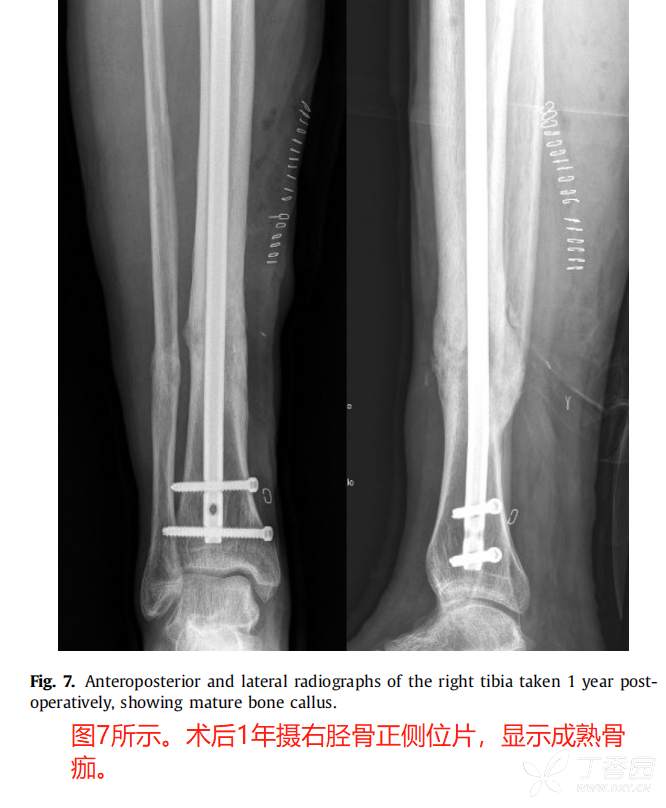

最近,国外采用Reamer灌洗吸引器系统(RIA, Depuy Synthes, West Chester, PA)从股骨髓腔进行扩孔已经成为一种常见的松质移植物来源。

在一些研究中,RIA技术的结果与更传统的髂骨移植进行了比较。Belthur等报道使用RIA后愈合率为90%,而髂骨移植后愈合率为80%。【5】此外,在本研究中,RIA组的疼痛评分较低,但髂嵴骨移植物摘除术后并发症发生率较高。

尽管潜在的骨移植替代物的研究一直在发展,自体骨移植仍然是治疗骨缺损的金标准。自体骨移植的愈合率高于替代骨移植。骨移植替代品的发展主要是为了减轻自体骨摘取的并发症。同时,RIA装置的发展和RIA在髓内骨移植中的应用显著减少了供骨区并发症。在可预见的未来,对于大多数骨不连,自体骨移植仍然是金标准。

典型病例: